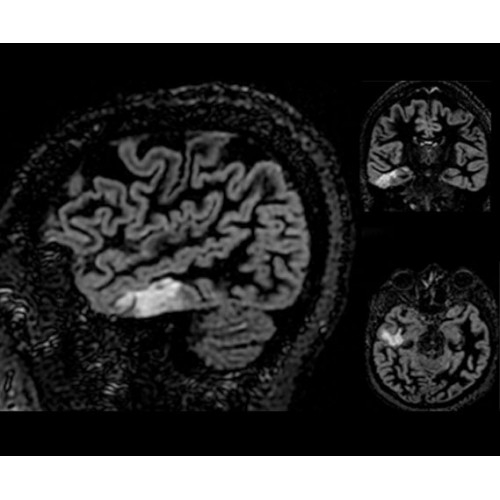

• NeuroWorks — универсальное решение для визуализации анатомии головного мозга, позвоночника, сосудов и периферических нервов с четкой дифференциацией тканей.

• SilentWorks — технология шумоподавления, которая снижает уровень шума для некоторых видов исследований до минимальных значений.

• ImageWorks — повысит производительность МРТ благодаря визуализации высокого качества с MAGIC, четкими результатами пост-процессинга с READYView.